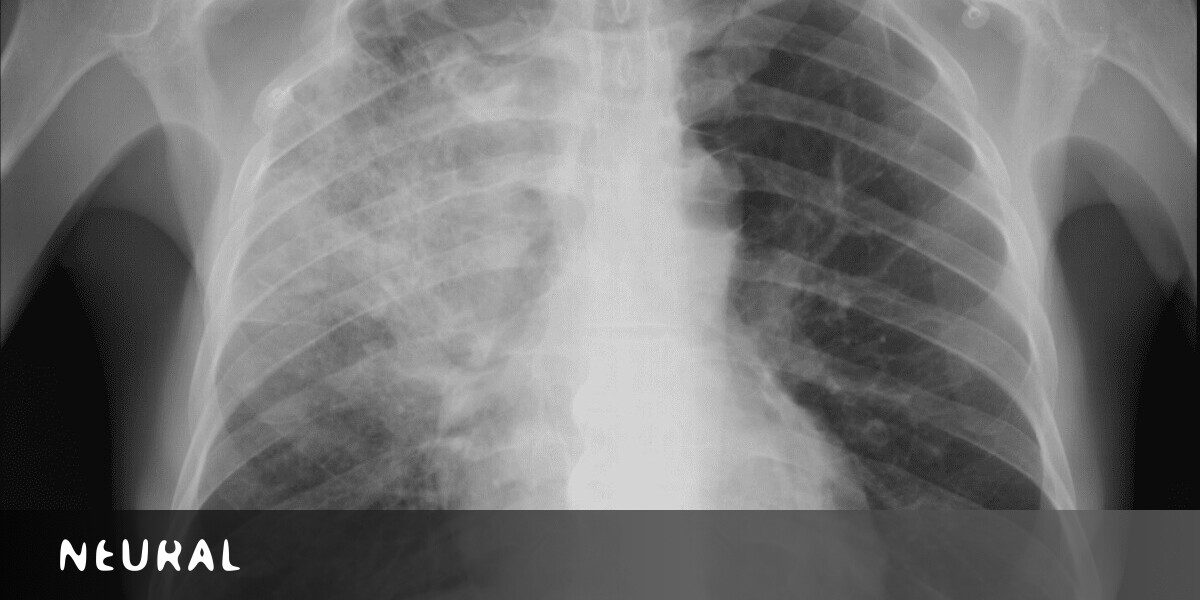

Body composition measurement in 9 11 y old children by dual energy x ray absorptiometry skinfold thickness measurements and bioelectrical impedance analysis. We compared in 9 11 y old children n43 three measures of body composition. Thus analysis of x ray images of the body is a valuable medical diagnostic tool. The intraclass correlation coefficient icc bland altman procedure and spearman rank correlation were used to determine test retest reliabilities of the three methods and to compare methods. The dxa scan is typically used to diagnose and follow osteoporosis as contrasted to the nuclear bone scan which is sensitive to certain metabolic diseases of bones in which bones are attempting to heal from infections fractures or tumors. The passage of x rays through materials including biological tissue can be recorded.

X ray electromagnetic radiation of extremely short wavelength and high frequency with wavelengths ranging from about 10 8 to 10 12 metre. Dexa machines are able to differentiate body weight into the components of lean soft tissue fat soft tissue and bone based on the differential attenuation by tissues of two levels of x rays. An x ray or x radiation is a penetrating form of high energy electromagnetic radiationmost x rays have a wavelength ranging from 10 picometres to 10 nanometres corresponding to frequencies in the range 30 petahertz to 30 exahertz 310 15 hz to 310 18 hz and energies in the range 124 ev to 124 kevx ray wavelengths are shorter than those of uv rays and typically longer than those of.